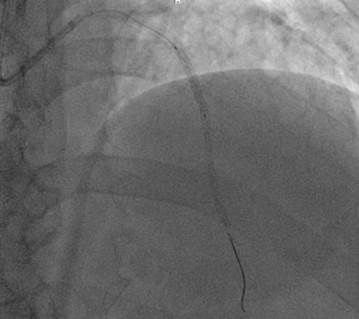

Los hallazgos fueron los siguientes:

· Tronco coronario izquierdo sin lesiones angiográficas significativas; descendente anterior (DA) estenosis severa entre tercio proximal y medio, suboclusiva; estenosis tercio distal coronaría derecha sin lesiones angiográficas significativas. (Ilustración 3 y 4).

Ilustración 4 Arteriografía coronaria izquierda, lesiones en arteria descendente anterior

Fuente: Hospital de Especialidades Guayaquil “Doctor Abel Gilbert Pontón”.

Se decidió realizar angioplastia coronaria percutánea a la DA colocándose 2 stent medicado 3 x 20 mm en tercio proximal y medio (Ilustración 5)

No hubo complicaciones durante el procedimiento.

Ilustración 5 Angioplastia con stent en descendente anterior.